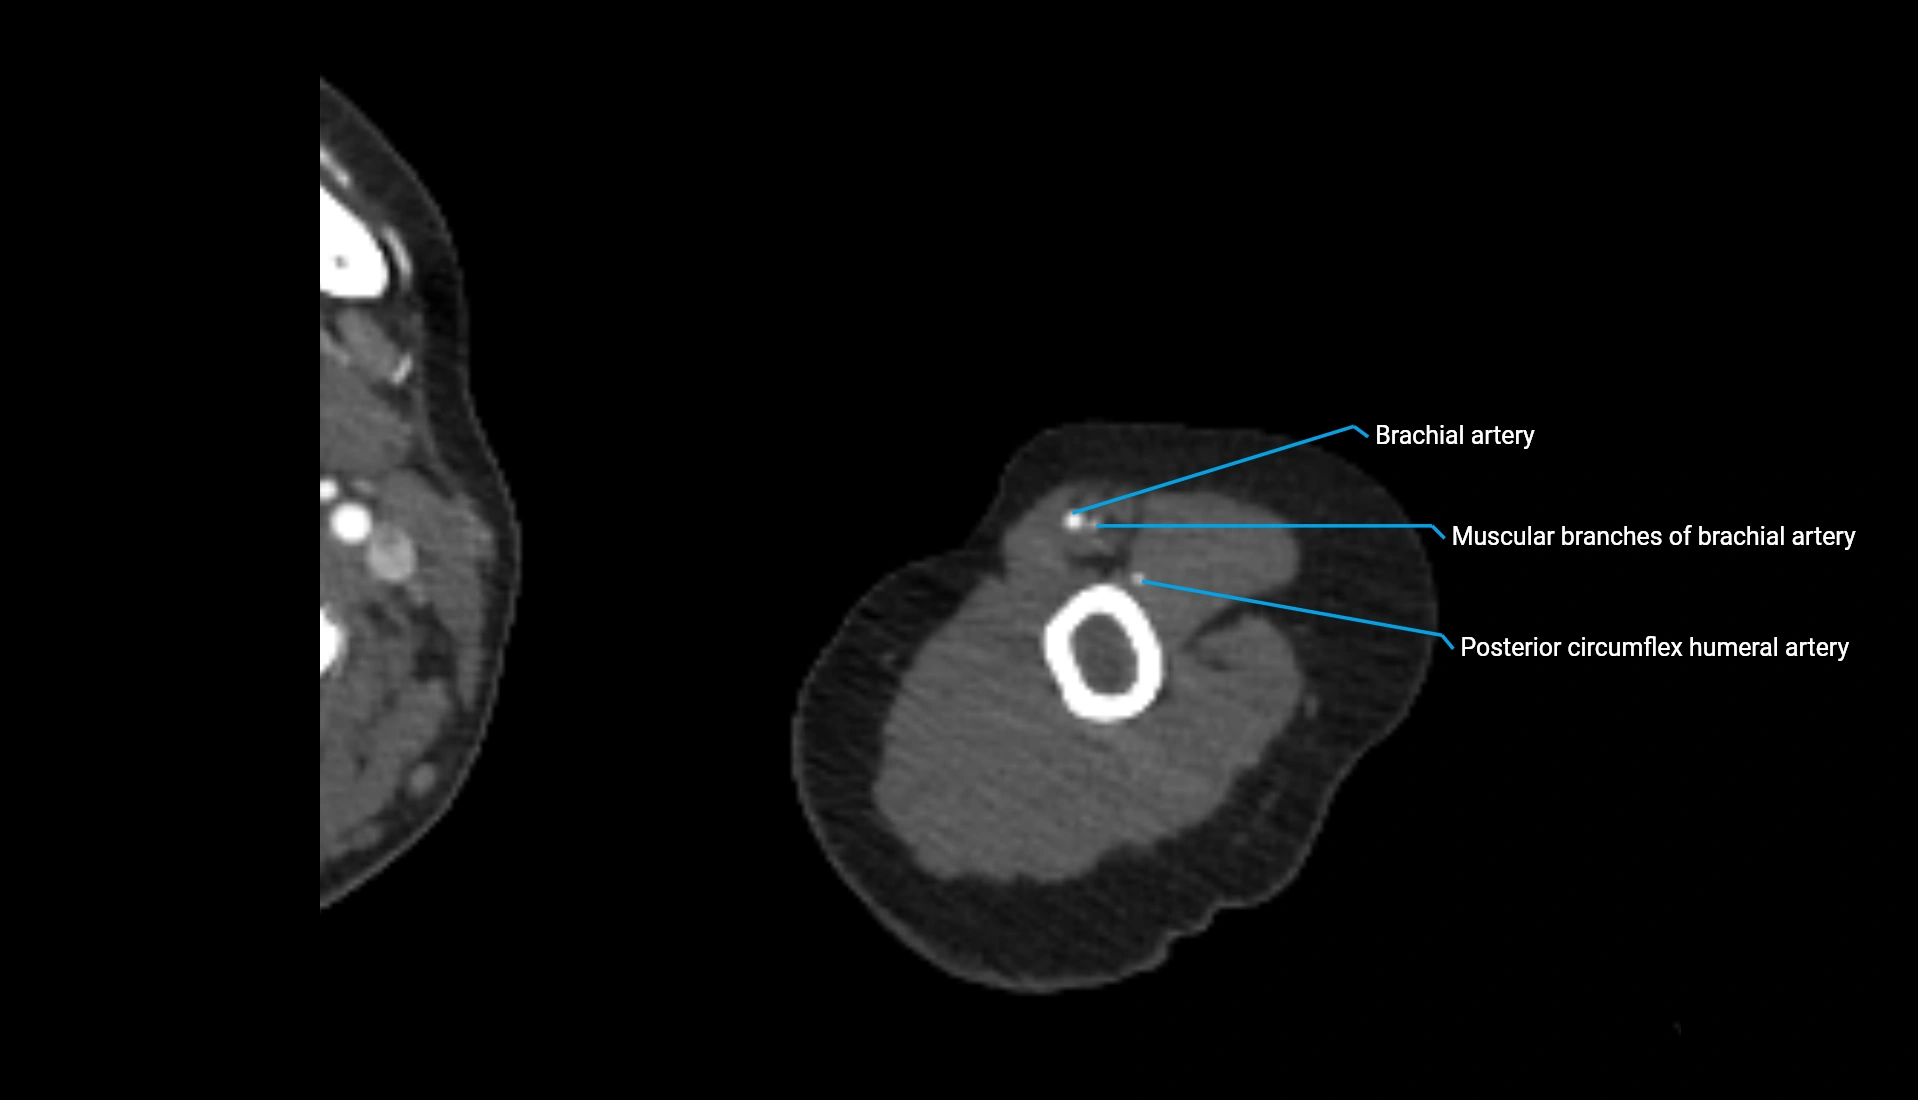

CT Appearance

Non-Contrast CT:

• Cortex: High-density, sharply defined

• Subchondral bone: Dense cancellous matrix

• Articular surface: Smooth concave contour articulating with the capitellum

• Excellent for evaluating bone integrity, alignment, and subtle fractures